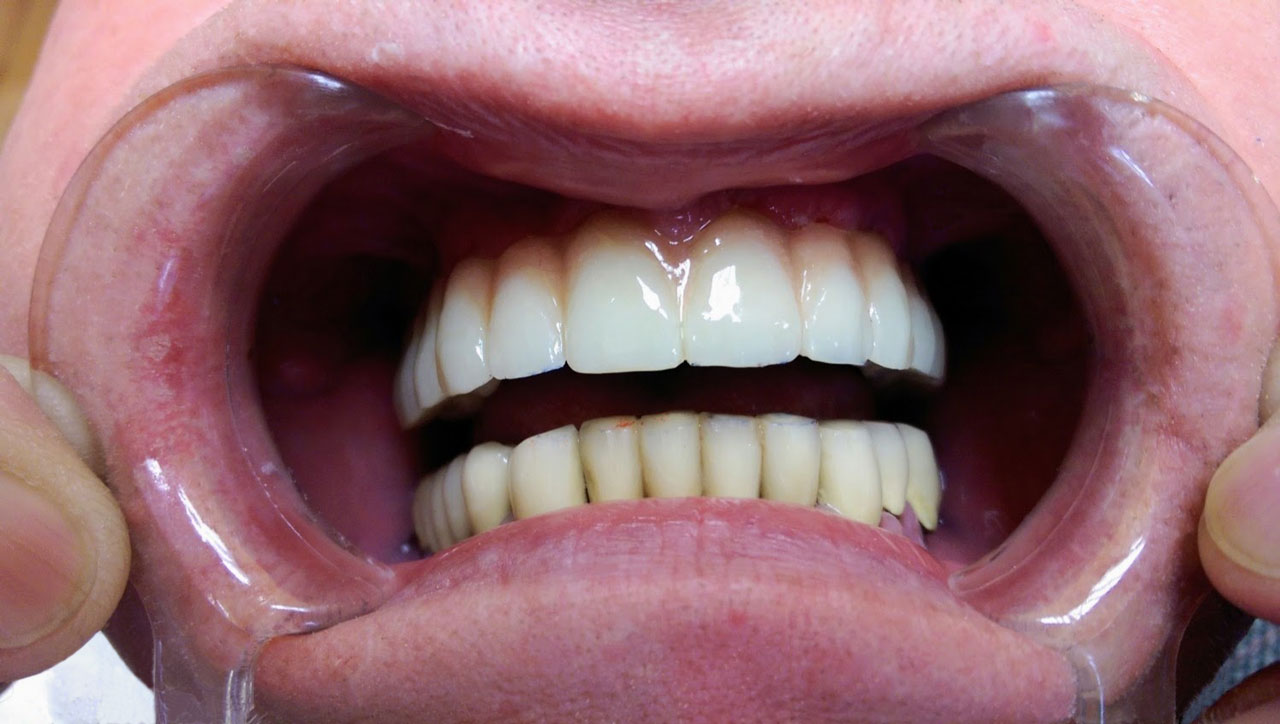

• esettanulmany-34

A felső állcsont teljes implantációs helyreállítása.

• esettanulmany-32

72 órávan a felső állcsont teljes implantációs helyreállítása után, így mosolyog a páciens a beragasztott, fix hiddal.